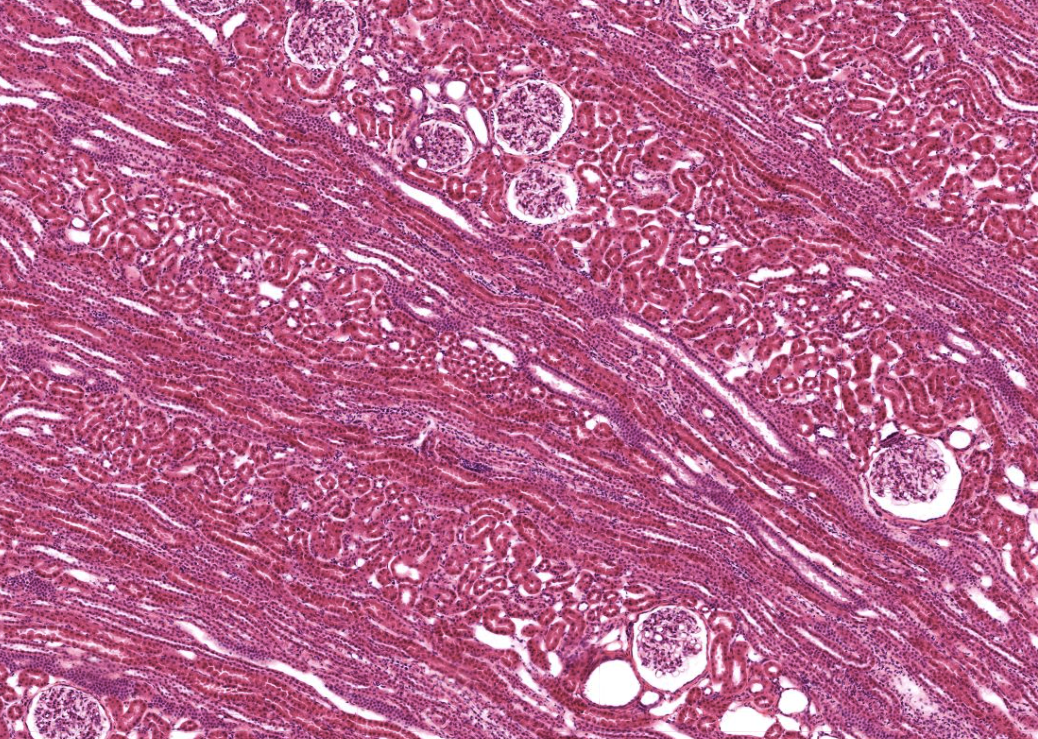

Kännetecken Ser ut som tuber som går mellan bark och märg. Namnet är lite missvisande då de ligger i barken, inte i märgen. Vanliga lokaler I barken mellan kapsel och märgen. Funktion Leder primärurin genom tubuli från barkens Nefron mot märgen. Relaterat Njurbark Njurmärg Nefron